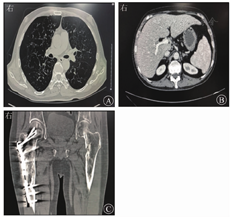

体格检查示体温为36.8 ℃,脉搏为92次/min,呼吸频率为20次/min,血压为131/98 mmHg,BMI为20.76 kg/m2;神志清楚,皮肤、巩膜黄染,无肝掌、蜘蛛痣;头顶部可见散在红色丘疹;左外耳道可见脓性分泌物,左侧颈后胸锁乳突肌后缘可触及1枚大小约0.5 cm×0.5 cm的淋巴结,质硬,表面光滑,有压痛,活动度可;双肺呼吸音清晰,未闻及干湿性啰音;心率为92次/min,律齐,各瓣膜听诊区未闻及杂音;腹平坦,无压痛、反跳痛和肌紧张,肝脾未触及;右股部可见一长约10 cm的手术瘢痕。入院血常规示白细胞计数为9.59×109/L,中性粒细胞占比为0.799,血红蛋白为125 g/L,血小板计数为456×109/L。尿常规检查示尿比重值为1.004,尿渗透压为68 mOsm/(kg·H2O)。粪便常规、凝血常规检查均未见异常。ESR为70 mm/1 h,超敏CRP为104.8 mg/L。感染相关指标如结核分枝杆菌、布鲁氏菌、伤寒沙门菌等细菌或真菌均呈阴性。肝功能检查示TBil为82.00 μmol/L,DBil为44.4 μmol/L,白蛋白为31.2 g/L,ALT为25 U/L,AST为30.0 U/L,ALP为910 U/L,GGT为287 U/L,总胆汁酸为18.4 μmol/L;肾功能、电解质、心肌酶、血糖、血脂均未见异常。病毒性肝炎标志物均呈阴性。自身抗体[包括抗核抗体、抗干燥综合征A(Sjögren syndrome A,SSA)抗体等]、抗线粒体抗体(anti-mitochondrial antibody,AMA)、AMA-M2、风湿因子均呈阴性。免疫球蛋白(immunoglobulin,Ig)G、IgM、IgA均无异常,补体C3为2.02 g/L,补体C4为0.41 g/L。CA125为37.2 U/mL,铁蛋白为244.72 μg/L。甲状腺功能3项(促甲状腺激素、游离甲状腺素和游离三碘甲状腺原氨酸)检查均无异常。垂体激素6项(促甲状腺激素、促卵泡生成素、促黄体生成素、促肾上腺皮质激素、生长激素、泌乳素)检查示,促甲状腺激素为7.020 mU/L,泌乳素为19.76 μg/L,余4项指标均无异常。腹部超声提示肝大,肝回声增粗;肝右叶囊肿;脾大。胸部CT平扫检查示两肺内多发大小不等的囊性病变,部分融合,两肺内散在慢性炎症性病变;左侧第6肋骨局部小类圆形异常密度影(图1A),性质待定。肺功能检测示中度阻塞性通气功能障碍,轻度限制性通气功能障碍,重度弥散功能下降。上腹CT平扫和增强CT检查示肝实质内多发低密度影(图1B),性质待定,暂考虑囊肿可能性大;肝门区和腹膜后多个淋巴结,部分稍大;胆囊壁稍增厚,胆汁淤积。骶髂关节CT平扫检查示符合右股骨术后改变,右股骨骨质密度欠均匀;左侧髋臼和左股骨多发骨质破坏伴周围软组织影(图1C)。

影像科颜立群副主任医师:本例患者的影像学表现特点如下:①肺CT表现为两肺弥漫性囊性病变,大小不等、部分融合,主要在肺外围,不累及胸膜;②骨组织为多灶性溶骨性破坏,伴周围软组织影,似有葱皮样骨膜反应,无硬化表现;③肝脾、淋巴结CT表现为肝内多发低密度病变,脾脏未见异常,肝门区和腹膜后淋巴结大。根据患者病史和上述影像学表现,同意张晓岚医师关于LCH和脂质肉芽肿病诊断可能。患者两肺弥漫性囊性病变,主要位于肺外围,不累及胸膜,骨质破坏为溶骨性破坏,肝内多发低密度病变,淋巴结大,符合LCH影像学表现,不支持点为肝脏多发低密度病变强化期未见强化。脂质肉芽肿病也可出现肺囊性病变、溶骨性破坏、肝脏多发低密度病变、淋巴结大,但对称、平滑的小叶间隔增厚和局灶性胸膜下实变是其更常见的肺部CT表现;其骨骼受累的经典影像学表现为骨质硬化,偶有溶骨和硬化病变混合存在。综上考虑LCH可能性大。